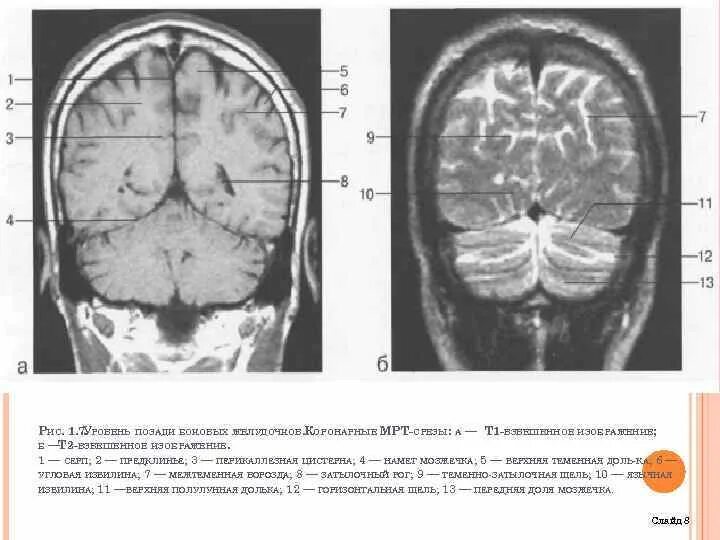

Цистерны на кт